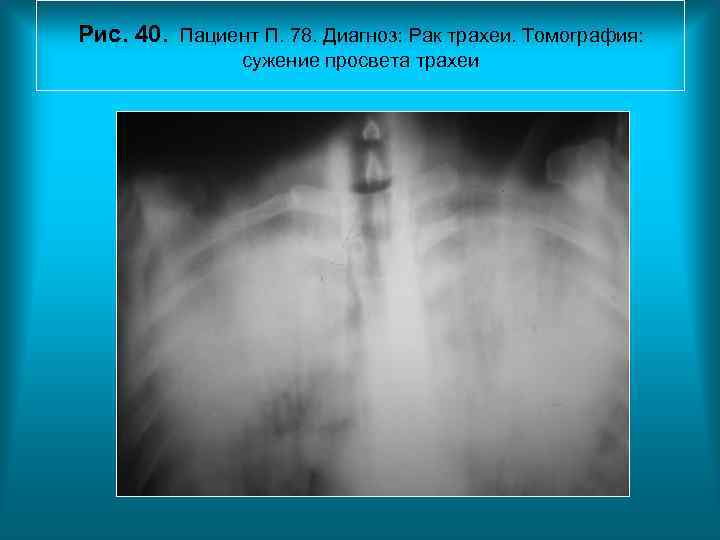

Рис. 40. Пациент П. 78. Диагноз: Рак трахеи. Томография: сужение просвета трахеи